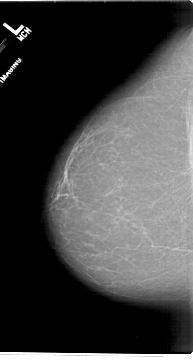

A_1716_1.LEFT_CC

LEFT_CC LINES 6871 PIXELS_PER_LINE 3661 BITS_PER_PIXEL 12 RESOLUTION 43.5 NON_OVERLAY